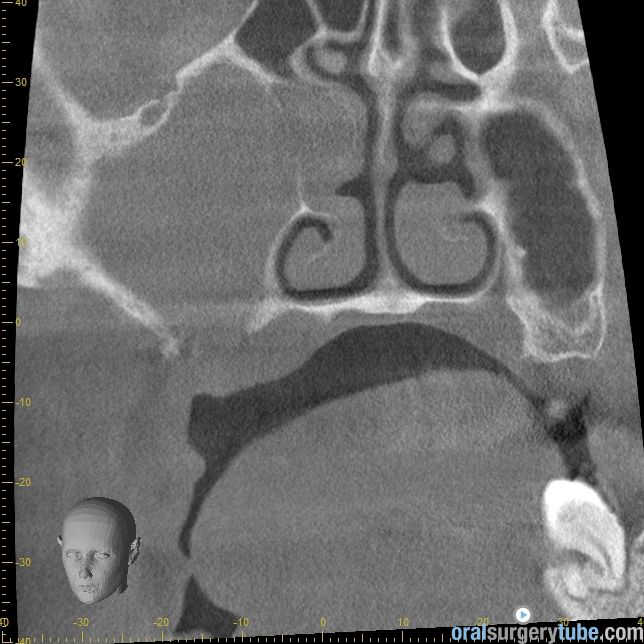

Cierre de comunicación orosinusal con tejido duro y blando